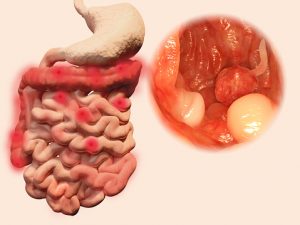

Individuals with inflammatory bowel disease (IBD) have 1.5 times higher risk of developing colon cancer, compared to the general population.

Roughly 15 percent of colon cancers are diagnosed within the first seven years of IBD diagnosis. It is also well known that chronic inflammation plays a role in colitis-associated cancer.

Annually, 147,000 new colon cancer cases are diagnosed, leading to 57,000 deaths. Inflammatory bowel disease, like ulcerative colitis and Crohn’s disease, causes inflammation along any part of the digestive system from the mouth all the way to the anus. Individuals with IBD are at a higher risk of colorectal cancer, compared to the general public.

Two main factors affecting the risk for colon cancer in IBD patients are the duration of the disease and the extent to which the colon is involved. The risk of colon cancer doesn’t begin to rise in IBD patients until eight to 10 years post-diagnosis. Furthermore, if the entire colon is inflamed or affected, that increases the patient’s risk of colon cancer, too.